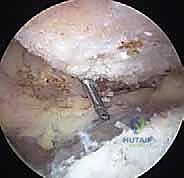

4. الاستئصال العظمي الدقيق (Bone Resection - The Mumford Procedure):

هنا تتجلى خبرة الجراح. الهدف هو إزالة جزء صغير جداً من نهاية عظم الترقوة (الطرف البعيد).

* يتم استخدام أداة قطع عظمية دقيقة جداً (Arthroscopic Burr).

* الكمية المستأصلة حاسمة: يقوم الدكتور هطيف بإزالة حوالي 5 إلى 8 ملليمترات فقط من العظم. إزالة كمية أقل قد لا تحل مشكلة الاحتكاك، وإزالة كمية أكبر (أكثر من 10 ملم) قد تؤدي إلى عدم استقرار المفصل وتضرر الأربطة الغرابية الترقوية (CC ligaments) الحيوية. الدقة هنا تقاس بالملليمتر.

* يتم تشكيل نهاية العظم المتبقية لتكون ناعمة ومسطحة، مع التأكد من إزالة جميع النتوءات العظمية العلوية والخلفية لمنع أي احتكاك مستقبلي.

5. التقييم الديناميكي والإغلاق:

بينما لا يزال المريض تحت التخدير، يقوم الدكتور هطيف بتحريك ذراع المريض في جميع الاتجاهات (خاصة حركة التقريب المتقاطع) وهو يراقب المفصل عبر الشاشة للتأكد من وجود مسافة كافية بين الترقوة والأخرم (حوالي 1 سم) وعدم وجود أي اصطدام أو احتكاك عظمي متبقي.